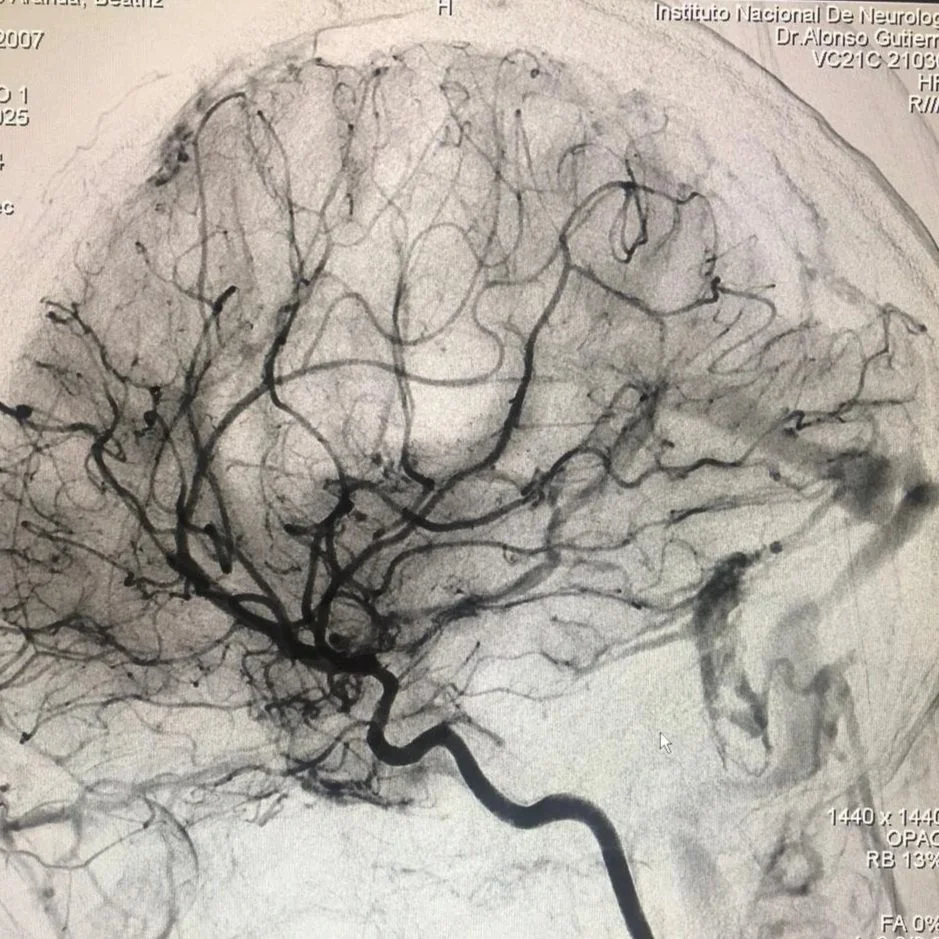

El Dr. Alonso Gutiérrez Romero, neurólogo en Cd. Mx. y especialista en terapia endovascular neurológica, ofrece evaluación integral y manejo avanzado de pacientes con infarto cerebral en entorno hospitalario de alta especialidad.